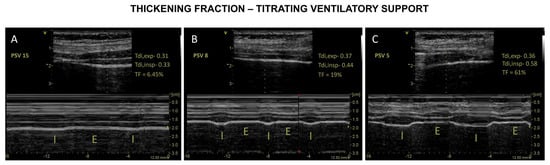

4.2.3. DUS to Monitor Effort–Diaphragm Protective Ventilation

- Umbrello, M.; Formenti, P.; Longhi, D.; Galimberti, A.; Piva, I.; Pezzi, A.; Mistraletti, G.; Marini, J.J.; Iapichino, G. Diaphragm ultrasound as indicator of respiratory effort in critically ill patients undergoing assisted mechanical ventilation: A pilot clinical study. Crit. Care 2015, 19, 161. [Google Scholar] [CrossRef]

- Vivier, E.; Mekontso Dessap, A.; Dimassi, S.; Vargas, F.; Lyazidi, A.; Thille, A.W.; Brochard, L. Diaphragm ultrasonography to estimate the work of breathing during non-invasive ventilation. Intensive Care Med. 2012, 38, 796–803. [Google Scholar] [CrossRef]

| Vivier,2012 [68] | # ICU, adult # Patients under planned NIV post-extubation # During SB and NIV (PS 5, 10, 15) # Pressure–time product (PTPdi) and USD (Tdi and TF) | 12 |

| # TF usefulness

|

| Goligher 2015 [45] | # ICU, adult patients requiring MV # TF at peak and end-inspiration (airway occluded and diaphragm relaxed) in 9 controls (at varying lung volumes). # EAdi and Pdi | 96 |

| TF significantly correlated with EAdi and Pdi (validation study) |

| Umbrello, 2015 [54] | # Surgical ICU, adult patients, after major elective surgery eligible for an SBT with PSV # PSV 0, 5 and 15 cmH2O). #TF and diaphragmatic excursion # Diaphragm and esophageal PTP (PTPdi and PTPes) | 25 |

| TF is a reliable indicator of respiratory effort in patients undergoing AMV DE should not be used to quantitatively assess diaphragm contractile activity. |

| Dube, 2017 [65] | # MV <24 h after intubation (‘initiation MV’), under ACV # MV at the switch to PSV (‘switch to PSV’) # Ptr,stim and US variables were measured in, and compared # DD = Ptr,stim < 11 cm H2O. | 112 | A TFdi < 29% could reliably identify diaphragm dysfunction (sensitivity and specificity of 85% and 88%) |